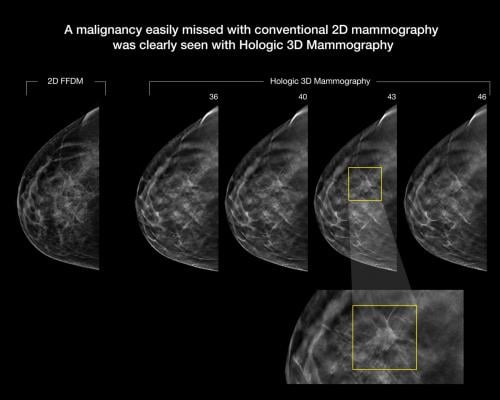

More Breast Cancers Found With Combined Digital Screening